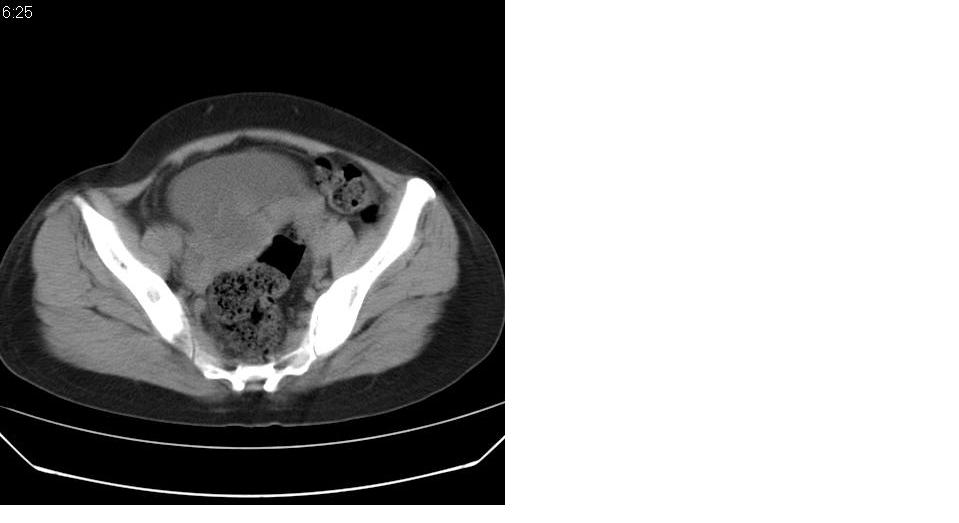

女 35岁,下腹部坠感疼,其它病史不详。图象顺序有点乱。

定位于盆腔附件,有囊性密度,有脂肪密度、还有骨密度;应该是比较典型的卵巢畸胎瘤。